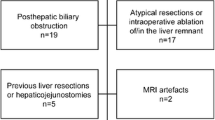

Patient Selection and Data Collection

All consecutive patients undergoing right-sided PVE with or without additional hepatic vein embolization (HVE) between 2018 and 2021 were included. All patients undergoing PVE had the approval of the interdisciplinary gastrointestinal tumor board.

A total of 53 consecutive patients (21 females, 32 males), with a mean age of 64 ± 10.5 years (range 22–82 years), receiving PVE prior to major hepatectomy were included in this study. Nineteen patients (35.8%) received simultaneous HVE in addition to PVE, additional segment IV embolization was performed in 9 (17.0%) patients, and 4 (7.5%) patients received HVE and segment IV embolization. Patients had various entities of primary or secondary liver cancer, such as perihilar cholangiocarcinoma (n = 14), intrahepatic cholangiocarcinoma (n = 8), gall bladder carcinoma (n = 5), hepatocellular carcinoma (n = 7), colorectal cancer (n = 14), non-seminomatous germ cell tumors (n = 1), uveal malignant melanoma (n = 1), liver adenoma (n = 1), immunoglobulin (Ig) G4-associated mass (n = 1, initially suspected cholangiocarcinoma), and solitary fibrous tumor (n = 1). Nineteen patients (35.8%) in the cohort had known liver steatosis, 16 (30.1%) had liver fibrosis, and 2 (3.8%) had liver cirrhosis. Eighteen patients (34.0%) had a history of chemotherapy due to underlying primary or secondary liver cancer prior to PVE. Baseline liver function tests prior to PVE were 0.9 ± 1.1 mg/dL for bilirubin, 59.7 ± 47.9 U/L for glutamic oxaloacetic transaminase (GOT), 66.0 ± 63.9 U/L for glutamic pyruvic transaminase (GPT), and 372.0 ± 384.3 U/L for gamma-glutamyl transferase (GGT). Mean body mass index (BMI) was 26.8 ± 5.2 kg/m2. Detailed patient characteristics are reported in Table 1.

To foster PVE response assessment and prediction, a dichotomous outcome parameter was defined as stated above: sufficient hypertrophy (increase of sFRL by ≥ 1.33) was reached in 35 (66%) patients, resulting in 18 (34%) patients remaining with a hypertrophy of < 1.33 after PVE. Of the 18 non-responders, 4 had received simultaneous PVE and HVE, of which only 1 patient proceeded to surgery in the long-term and did not show postoperative liver failure or mortality. Binary logistic regression did not identify any significant baseline characteristics (age, sex, height, weight, BMI, liver laboratory parameters, pre-existing liver disease, splenomegaly, prior chemotherapy, baseline volumetry, days after PVE to volumetry) to be predictive for achieving an sFRL hypertrophy of ≥ 1.33 (Table 1).